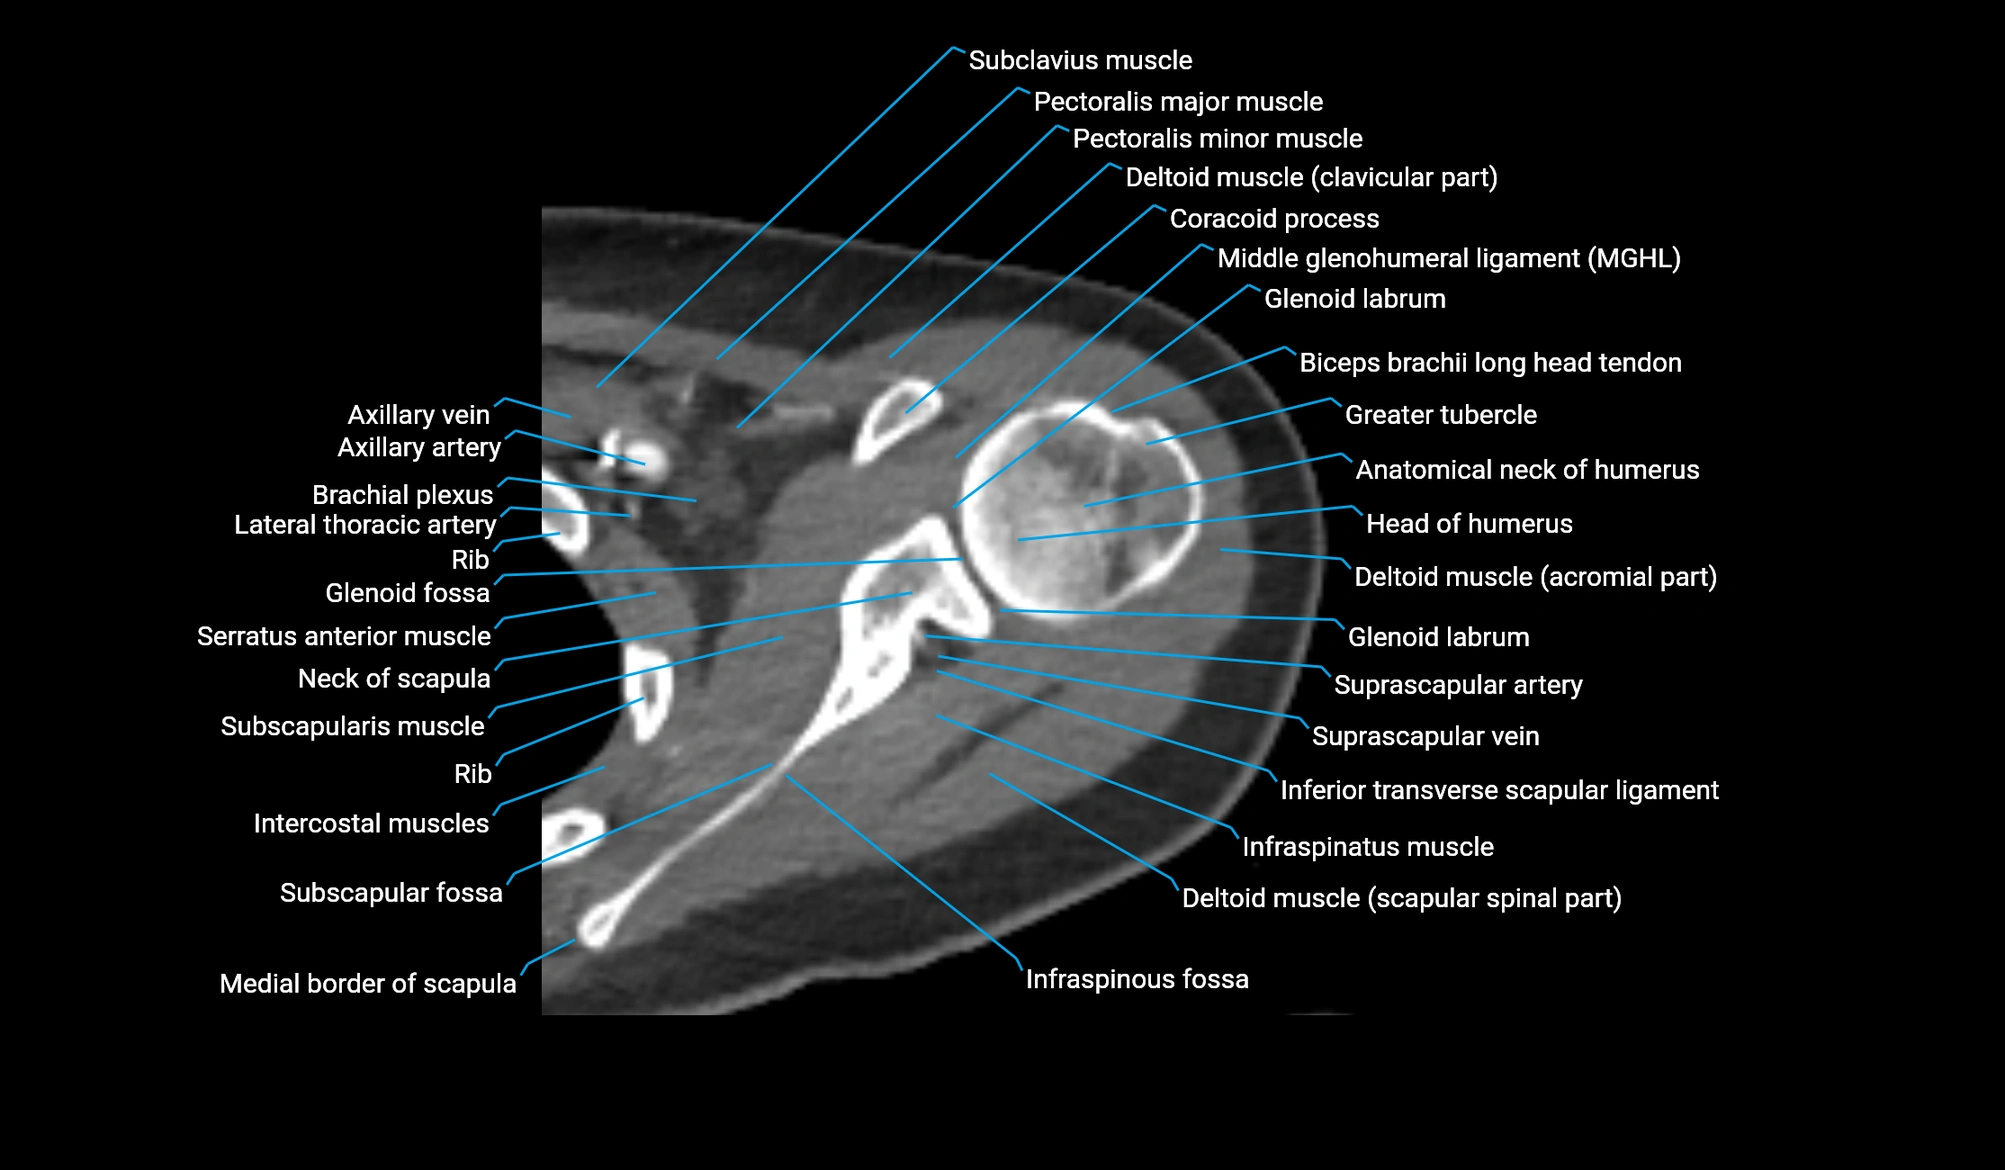

CT image